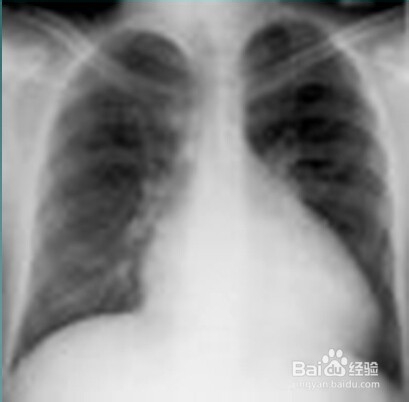

2、二:扩张型心肌病的X线图片。